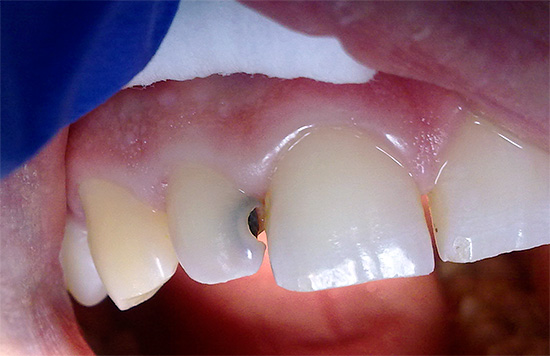

Quindi, cominciamo con il dolore, che sono segni caratteristici della carie. Già con le forme iniziali di carie, può apparire una sensazione di indolenzimento e una maggiore sensibilità dei fuochi di demineralizzazione dello smalto (cioè aree di smalto con componenti minerali parzialmente lavati). In questa fase, per prevenire un'ulteriore distruzione dei tessuti duri, è necessario prendere un ciclo di terapia rimineralizzante il più presto possibile (almeno, utilizzare dentifrici rimineralizzanti).

Tuttavia, il dolore severo può apparire solo quando la distruzione cariata raggiunge il confine smalto-dentina - in questo caso, i tessuti dei denti sono sensibili a varie sostanze irritanti (freddo, dolce, ecc.). In tali situazioni, per sbarazzarsi rapidamente delle sensazioni spiacevoli, è sufficiente eliminare semplicemente l'irritante e il dolore passerà immediatamente. Tuttavia, ovviamente, per un trattamento completo senza sigillo non sarà più sufficiente.

Il dolore nella carie media e profonda si verifica a causa del fatto che lo strato di dentina è penetrato da molti tubuli dentinali che alimentano il dente e ne determinano la sensibilità (e hanno anche una certa connessione con il "nervo" dentale). Quando lo strato di dentina viene distrutto, appare qualcosa come una "ferita" di dentina, che risponde all'azione degli stimoli.